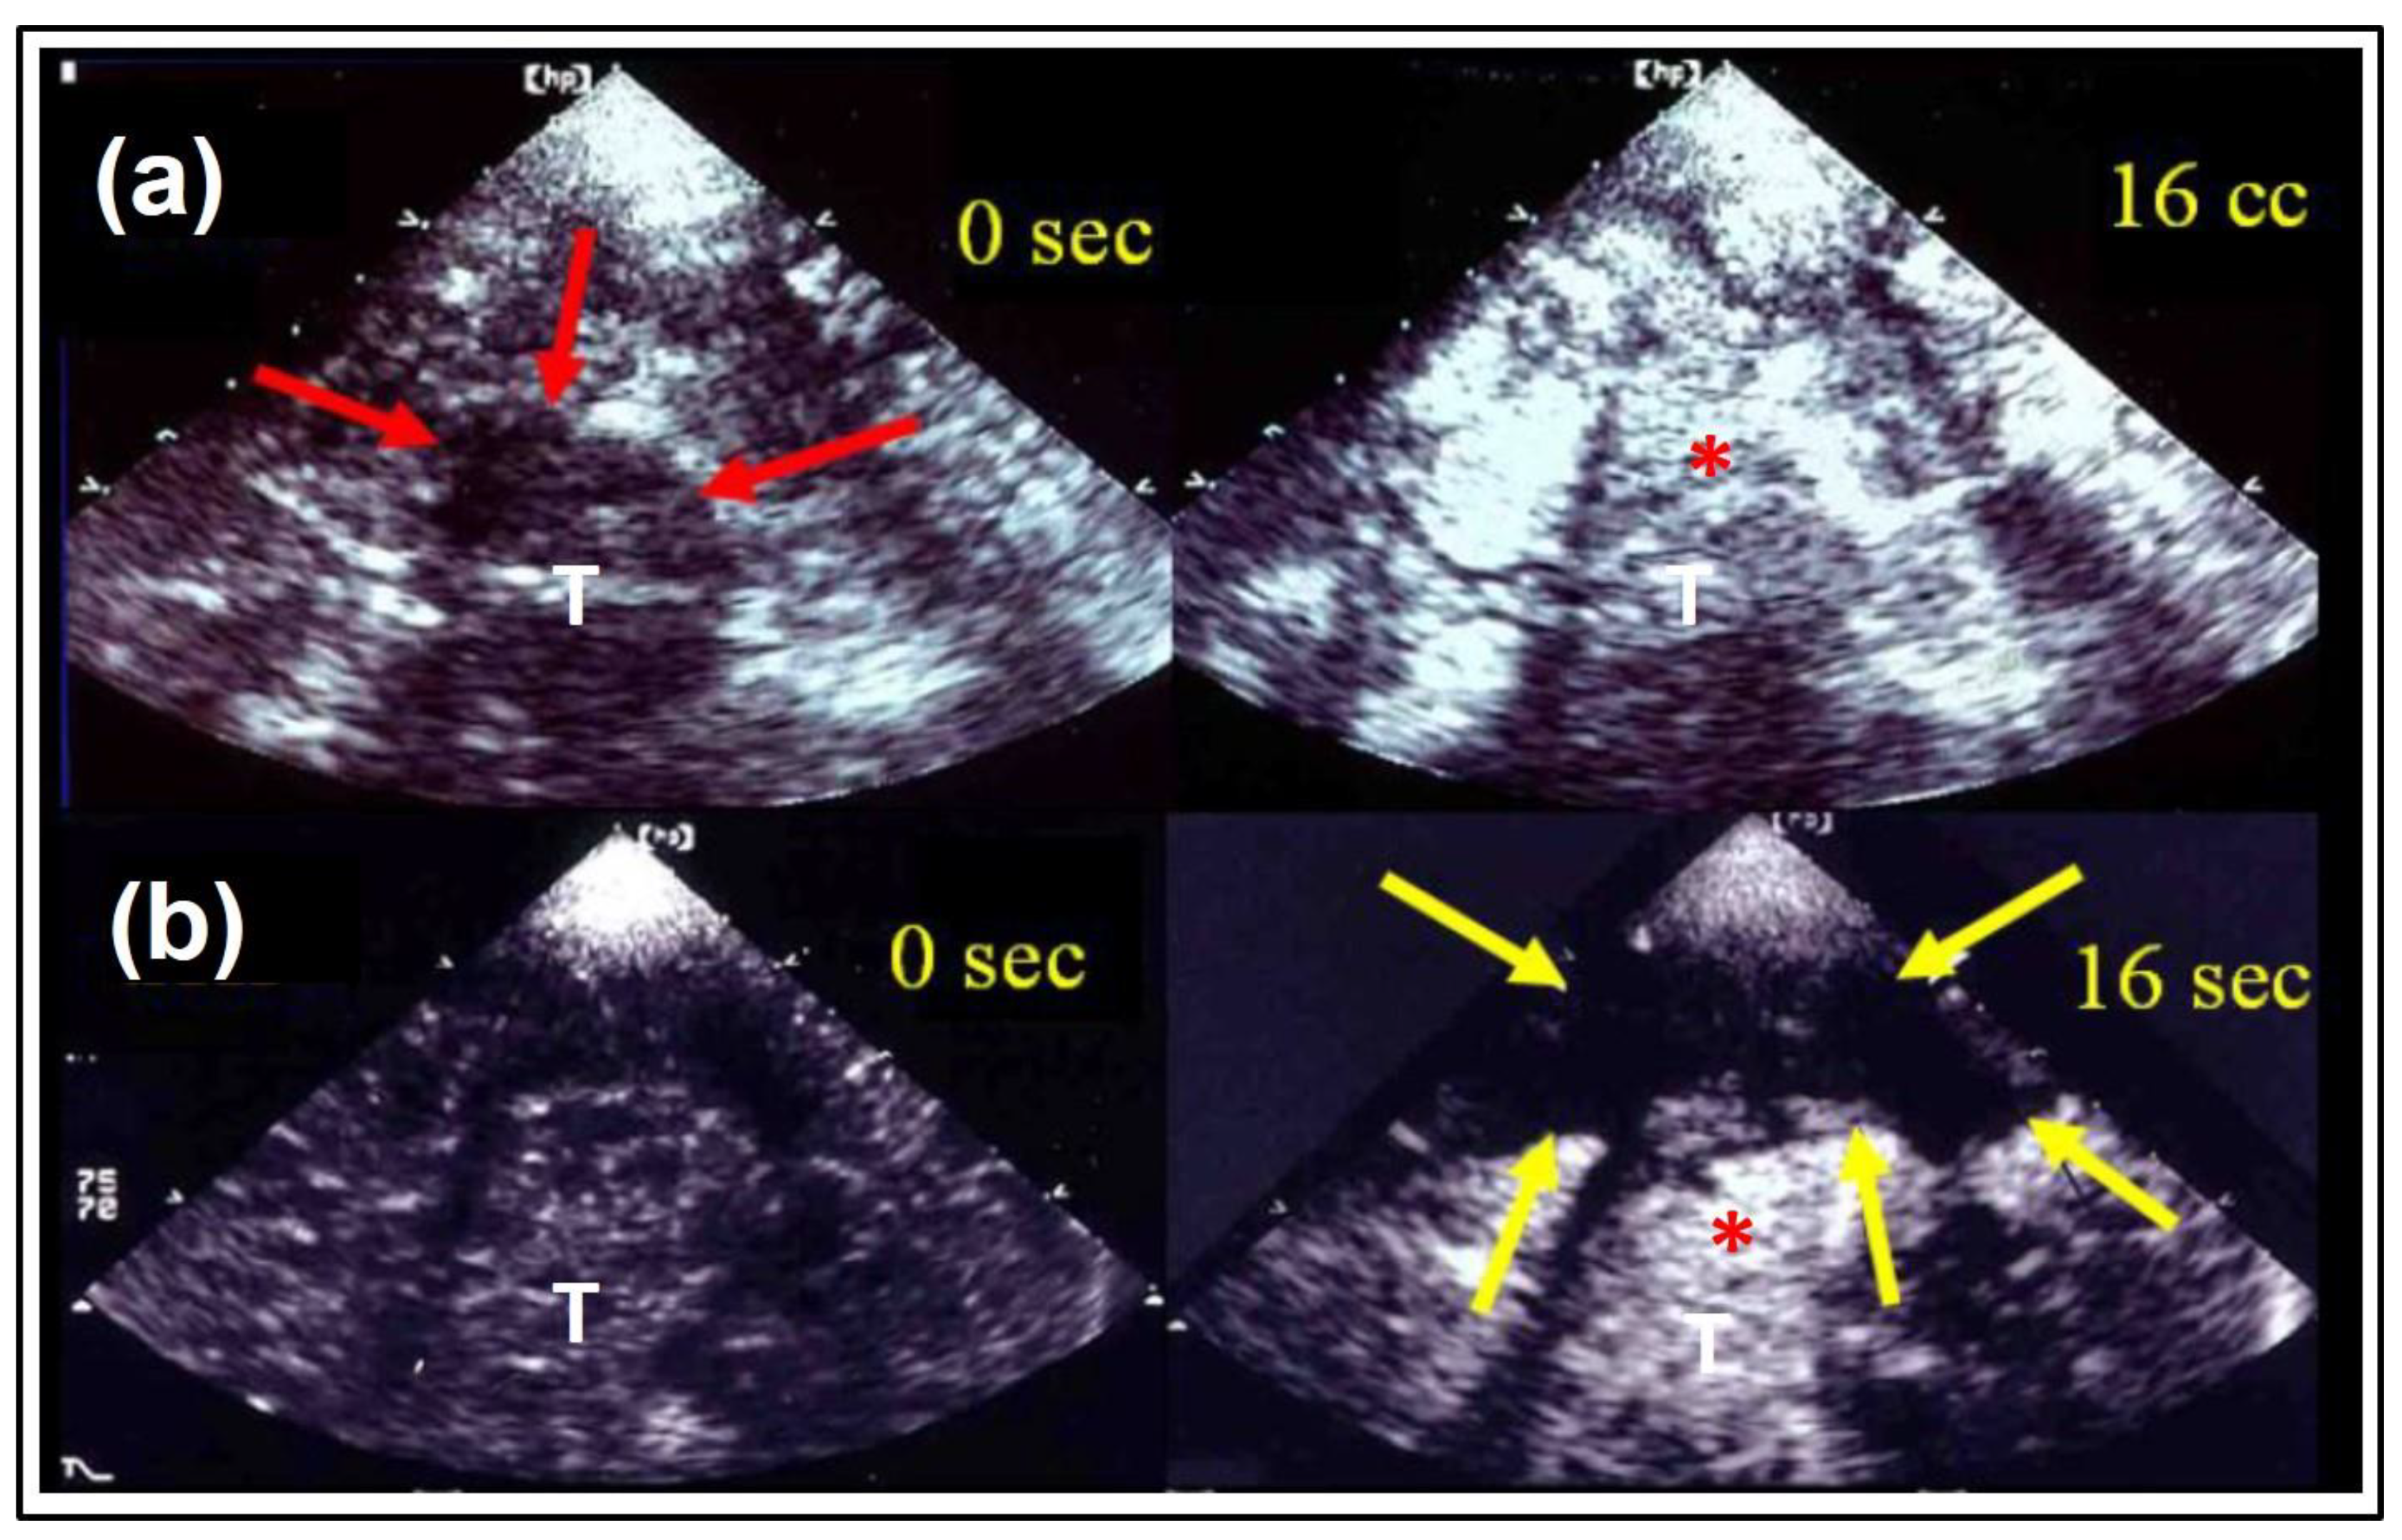

- Eyding, J.; Wilkening, W.; Reckhardt, M.; Schmid, G.; Meves, S.; Ermert, H.; Przuntek, H.; Postert, T. Contrast Burst Depletion Imaging (CODIM): A new imaging procedure and analysis method for semi-quantitative ultrasonic perfusion imaging. Stroke 2003, 34, 77–83. [Google Scholar] [CrossRef]